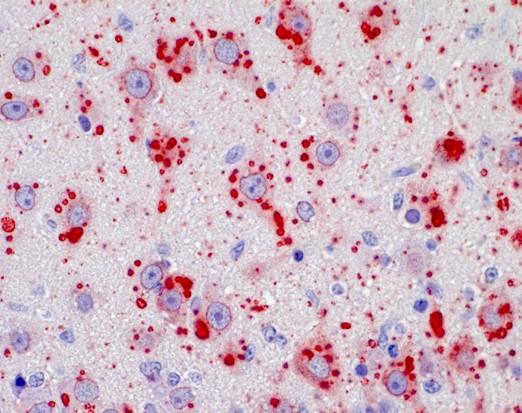

Direct fluorescent antibody (DFA) test

The DFA test demonstrates that animals with rabies have rabies virus- expressed proteins (antigens) in their tissues.

- Brain tissues are ideal for this test because rabies is present in nervous tissue (and not blood like many other viruses).

- Other innervated tissues may have antigens, but these tissues are less accurate at detecting rabies when compared to brain tissues.

- The most important part of a DFA test is fluorescently labeled anti-rabies antibody.

- When the labeled antibody is incubated with rabies-suspect brain tissue, it will bind to rabies antigen.

- Unbound antibodies can be washed away and areas where antigen is present can be visualized as fluorescent-apple-green areas using a fluorescence microscope.

- If rabies virus is absent, there will be no staining.

The DFA test has high sensitivity and specificity for detecting rabies and has been rigorously evaluated by international, national, and state health laboratories.

Direct rapid immunohistochemical test (DRIT)

The DRIT for rabies functions similarly to the DFA test in detecting the presence of rabies virus antigen in animal tissues. Like DFA, DRIT relies on observing rabies virus-expressed proteins in infected nervous system tissues.

- Brain tissue is ideal due to its high concentration of rabies antigen.

- Other innervated tissues may have antigens, but they are less accurate at detecting rabies when compared to brain tissues.

- The key component of the DRIT test is rapid immunohistochemical staining with anti-rabies antibodies.

- These antibodies are labeled with a chromogenic marker and when incubated with suspect tissue, the marker binds specifically to rabies antigen.

- Excess antibodies are then washed away, and areas containing rabies antigens appear in color under a light microscope.

- The absence of staining indicates the absence of rabies virus

Like DFA, DRIT boasts high sensitivity and specificity. It has been thoroughly evaluated by international, national, and state health laboratories.

Immunohistochemistry (IHC)

IHC methods are sensitive and specific for the detection of rabies virus antigen in formalin-fixed tissues. IHC testing is more sensitive and specific than histologic staining methods, such as hematoxylin and eosin (H&E) and Sellers stains.

- Brain tissues fixed in formalin must first be processed by routine histologic methods, embedded in paraffin, and sectioned to formalin-fixed paraffin-embedded slides.

- Rabies virus antigen is detected using specific anti-rabies monoclonal or polyclonal antibodies.